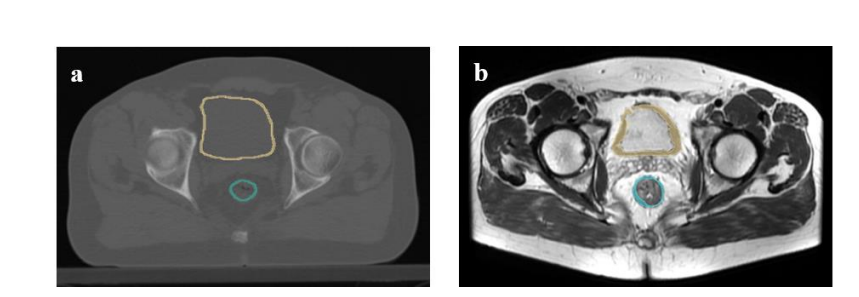

Figure2. Segmentation of the rectum and bladder walls on a) planning CT, b) pre-MRI T2W of therectal cancer patient in 3D-slicer.

图2. 在a) 规划CT、b) 直肠癌患者前MRI T2W上对直肠和膀胱壁的分割,使用3D切片器